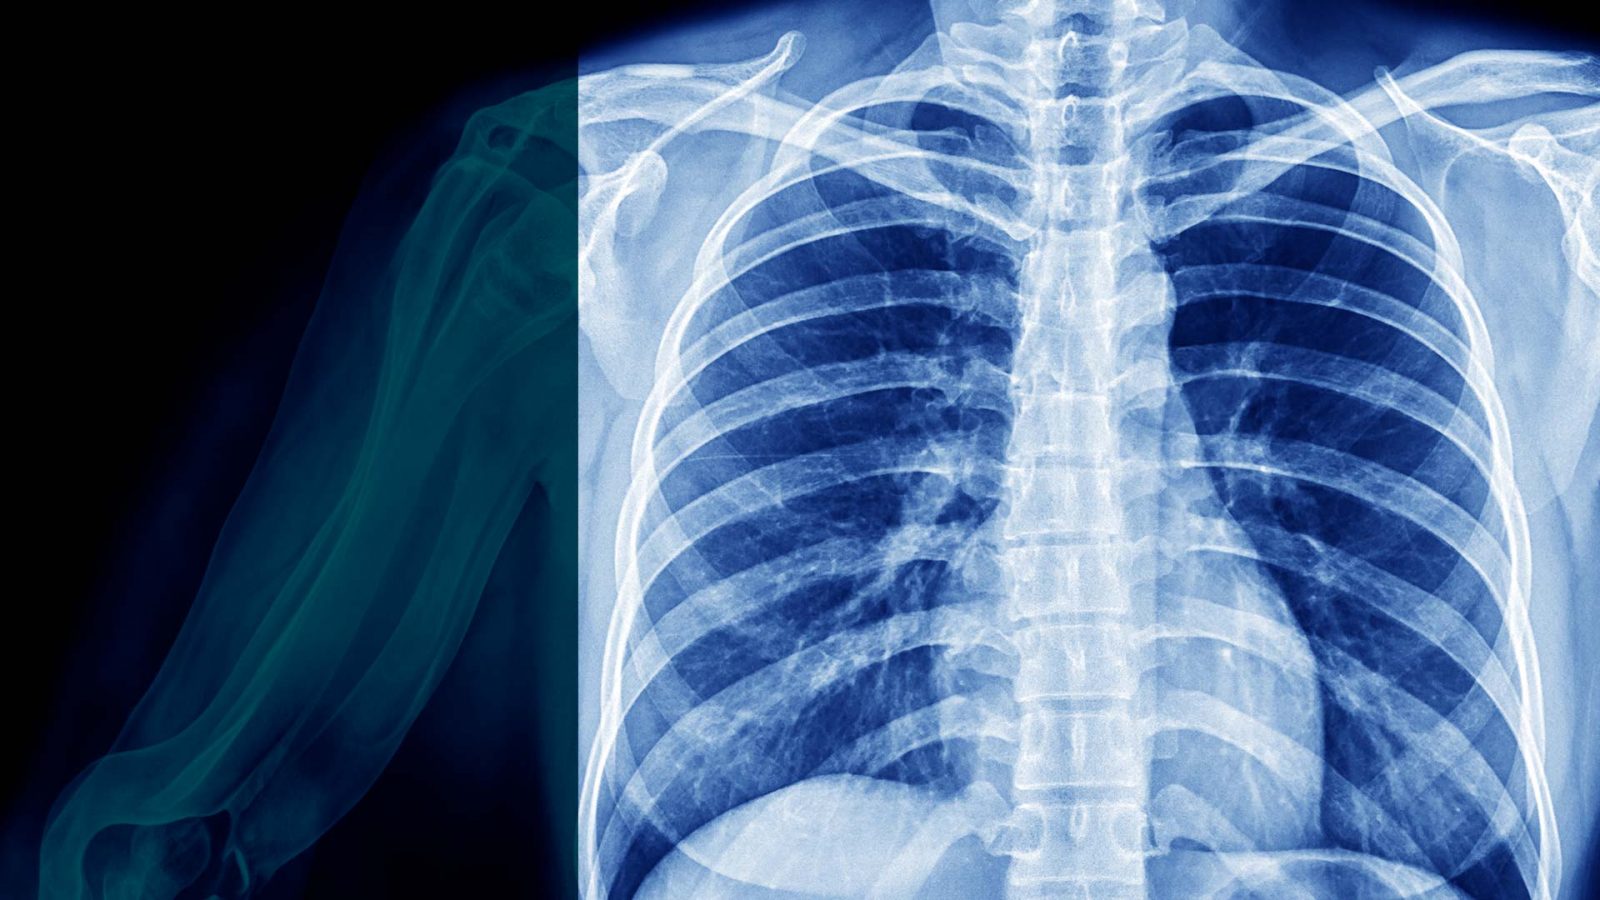

O derrame pleural é o acúmulo de líquido no espaço pleural, ou seja, no espaço existente entre as costelas e os pulmões.